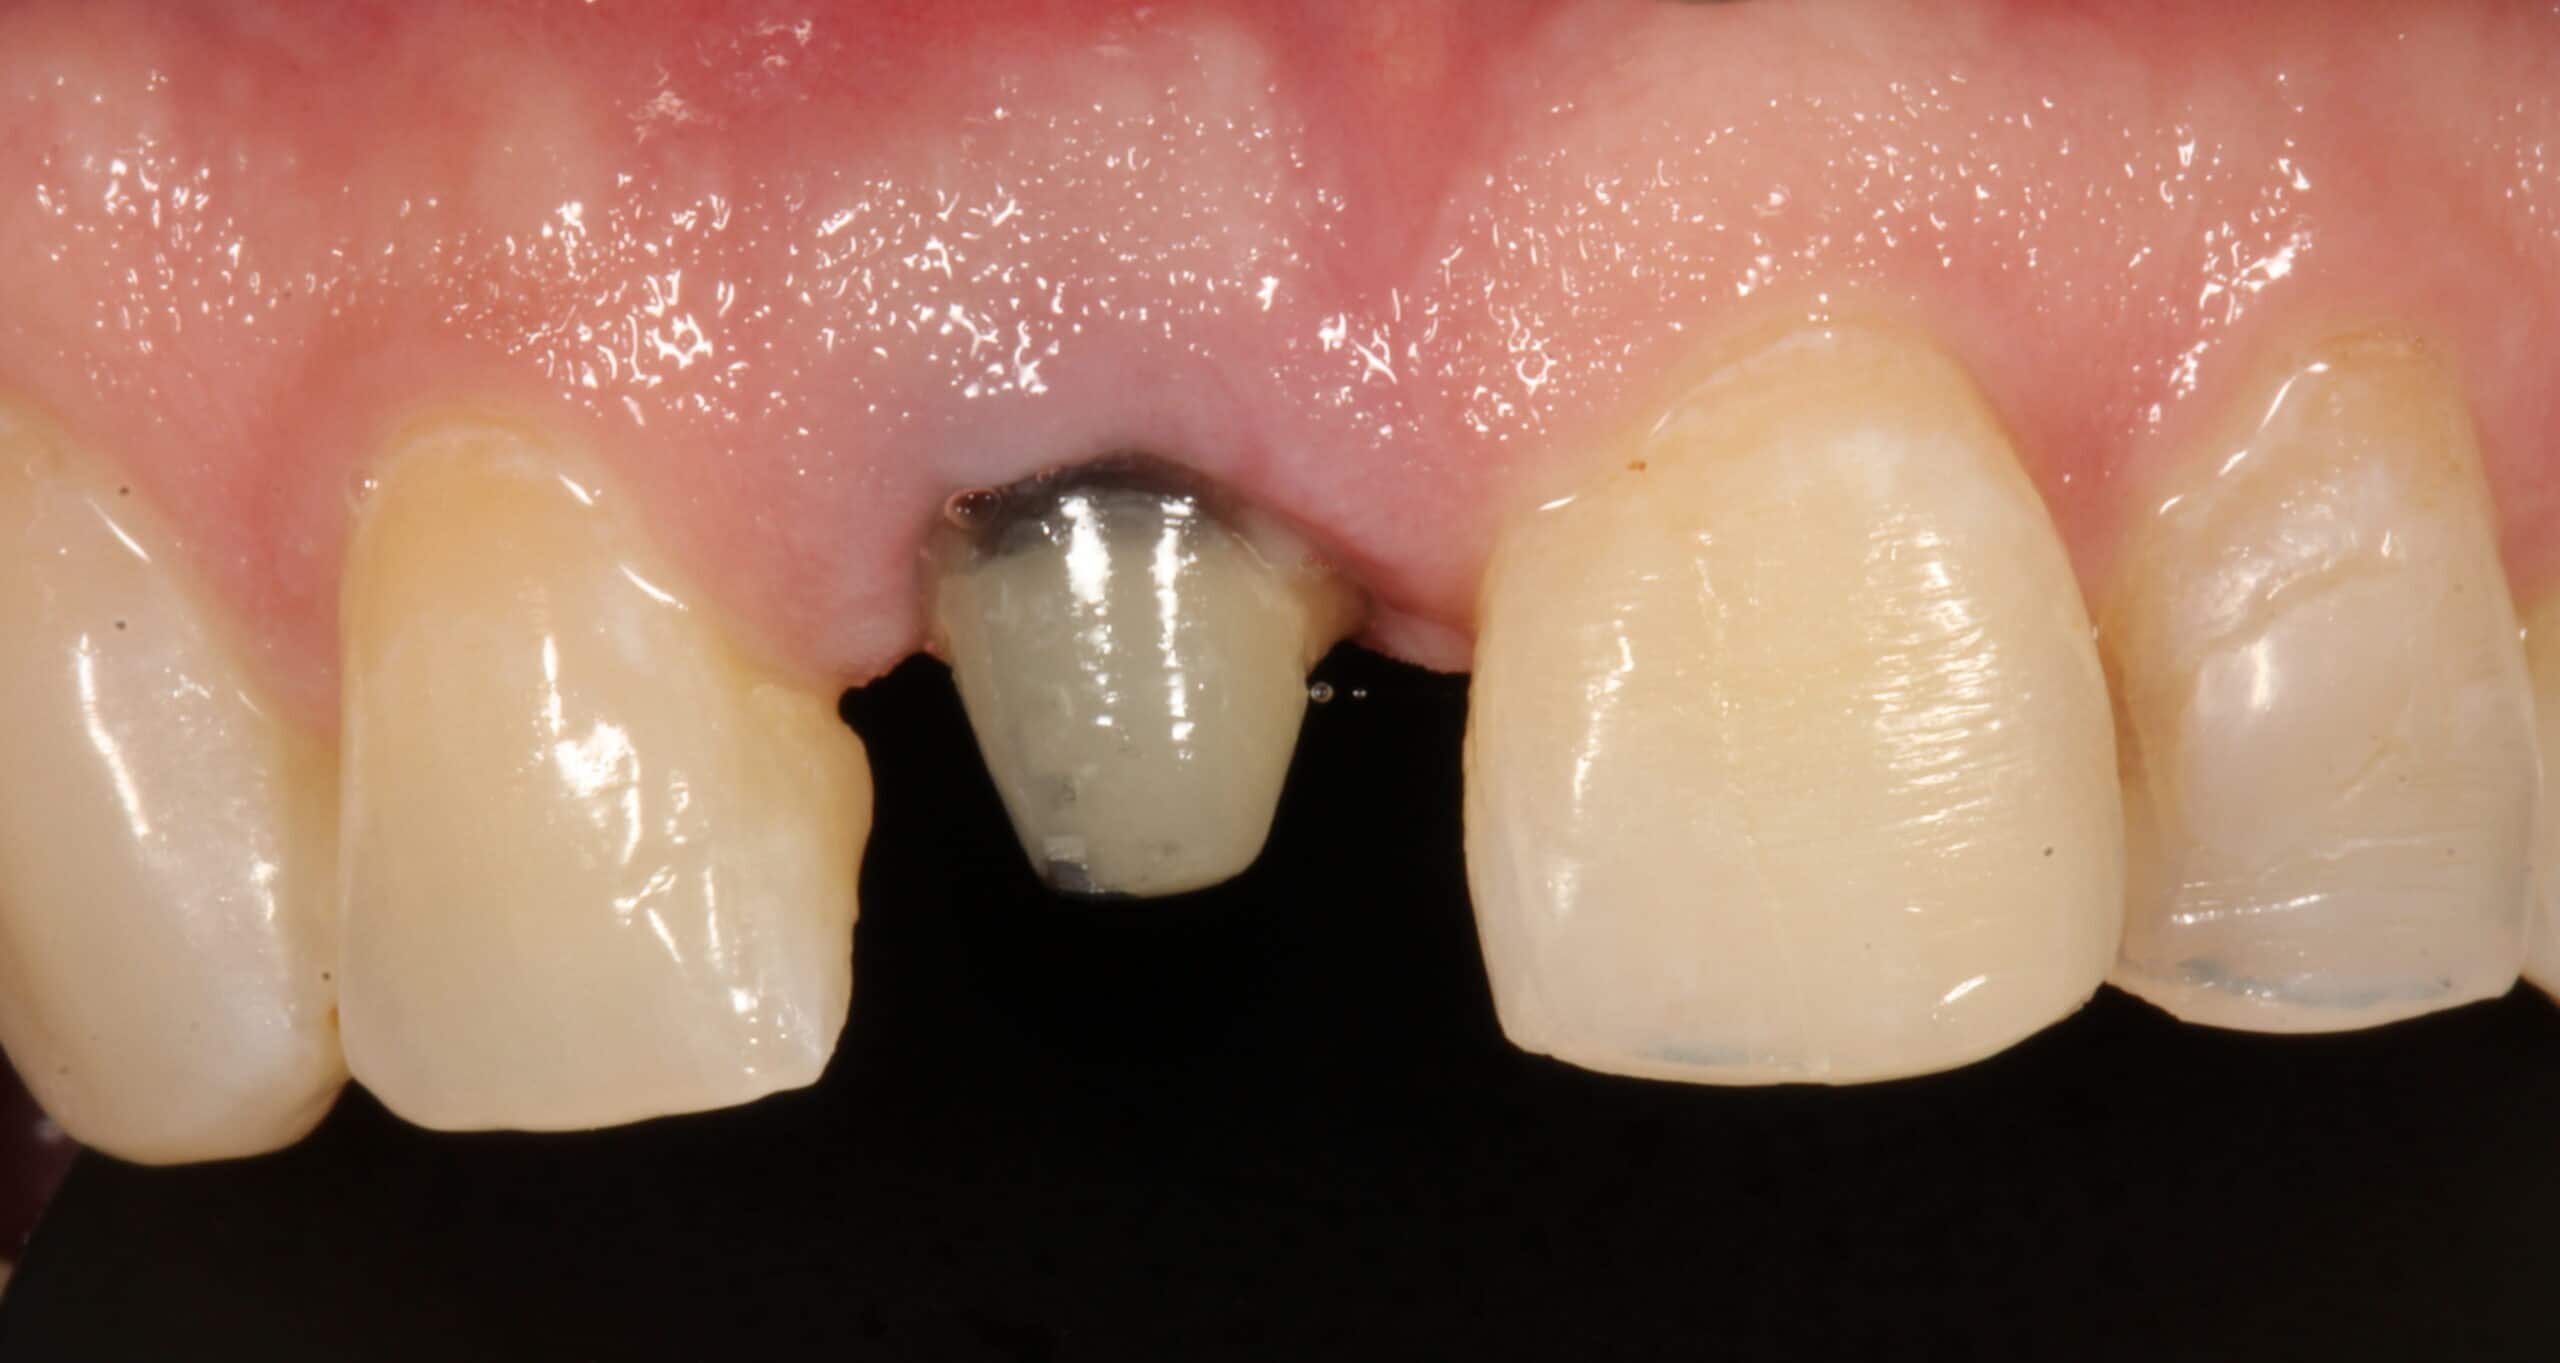

Our patient returned after his tooth was disinfected by a root canal specialist (Endodontist.) Dr. Peter Mann then placed a Rescue post in the tooth which will help hold the crown.

A digital impression was then taken with our Itero scanner for a porcelain crown. The patient left our office with a temporary crown held in place by the new post.